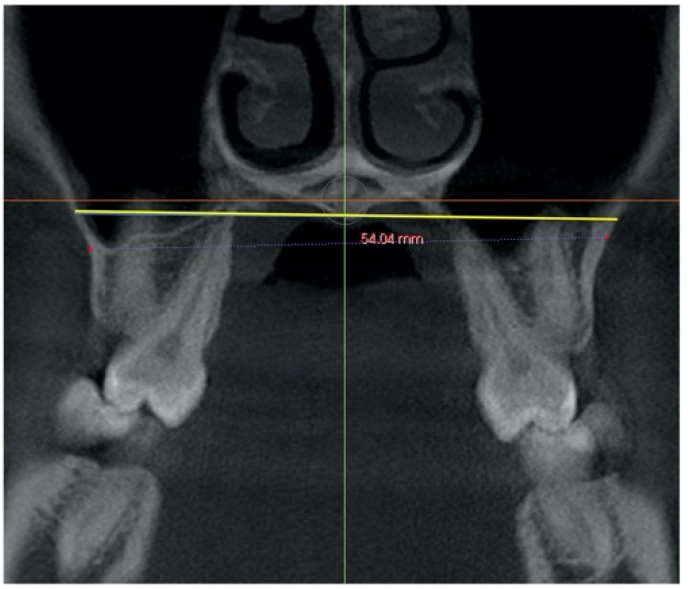

| Nasal width (NW) | Distance between right and left most lateral point of the nasal cavity in the coronal section at the level of first molar where total length of palatal root and crown are visualized. | ![]() |

| Maxillary width (MW) | Distance between the lowest point of lateral right and left contour concavities of the maxillary bone, on a coronal section, at the level of first molar where total length of palatal root and crown are visualized. | ![]() |